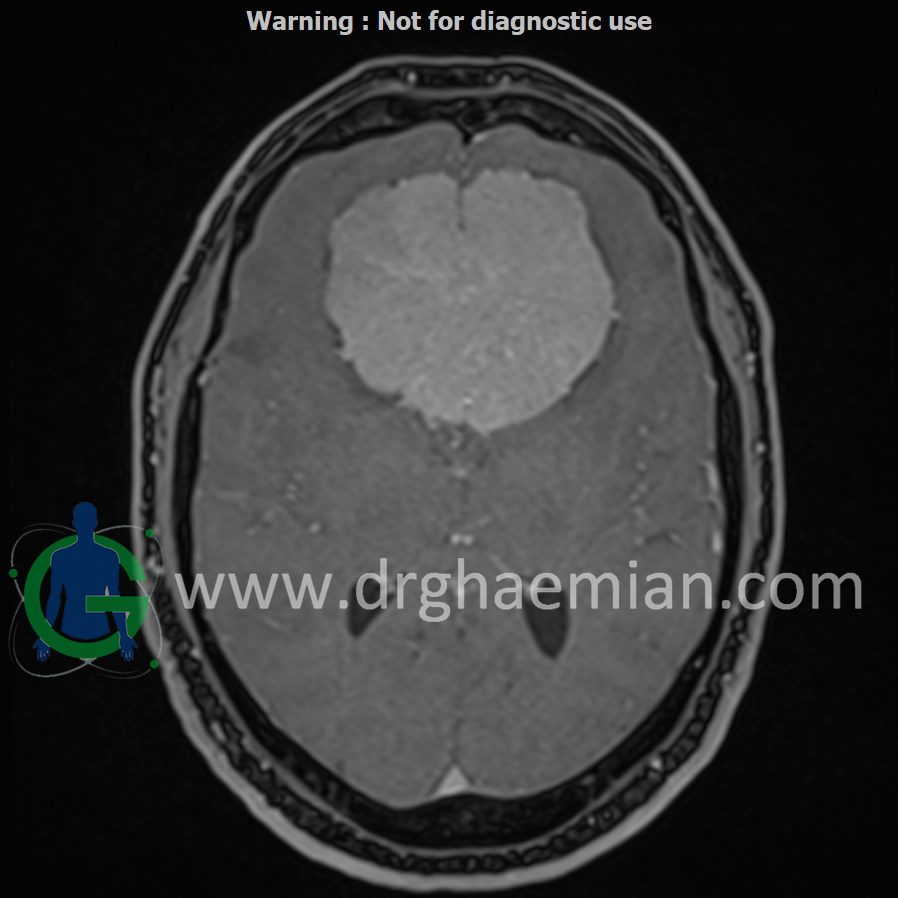

ام آر آی مغز یک روش تصویربرداری است که با استفاده از آهنربا های قوی و امواج رادیویی تصاویری از مغز و بافت های عصبی پیرامونی آن ایجاد می کند. در این کیس مننژیوما مغزی و …. دیده میشود

MRI OF BRAIN (WITH AND WITHOUT IV GADOLINIUM)

Multiplanar, multislice, and multisequence MR images of the brain were obtained before and after IV gadolinium administration. Findings:

Impression

1. Large, vividly enhancing extra-axial mass in the anteriorcranial fossa (49 × 63 × 73 mm) with “spoke-wheel” vessels, CSF cleft, and broad dural contact—findings suggestive of meningioma. 2. Imaging features favor a left olfactory-groove origin, with the lesion wrapping around the anteriorfalx. 3. Extensive frontal lobe vasogenic edema with mass effect effacing the frontal lobes, frontal horns, and the genu of the corpus

callosum, without hydrocephalus. 4. Posteroinferiorextension into the pituitary fossa while remaining separate from the pituitary gland. 5. Close approximation to both supraclinoid internal carotid arteries and contact with the anteriorcerebral arteries along the

posterosuperiorsurface. 6. Findings suspicious forinvasion of the roof of the left ethmoid sinuses (loss of cortical definition). 7. Otherwise unremarkable MRI brain.